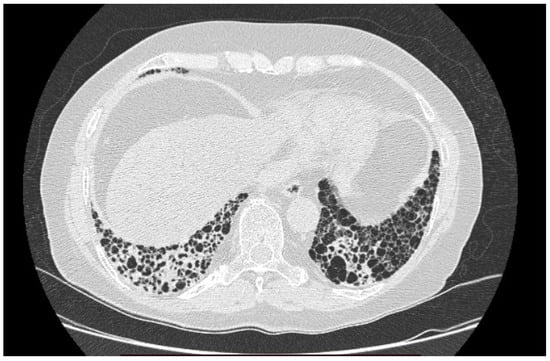

4.1.2. Radiological Testing